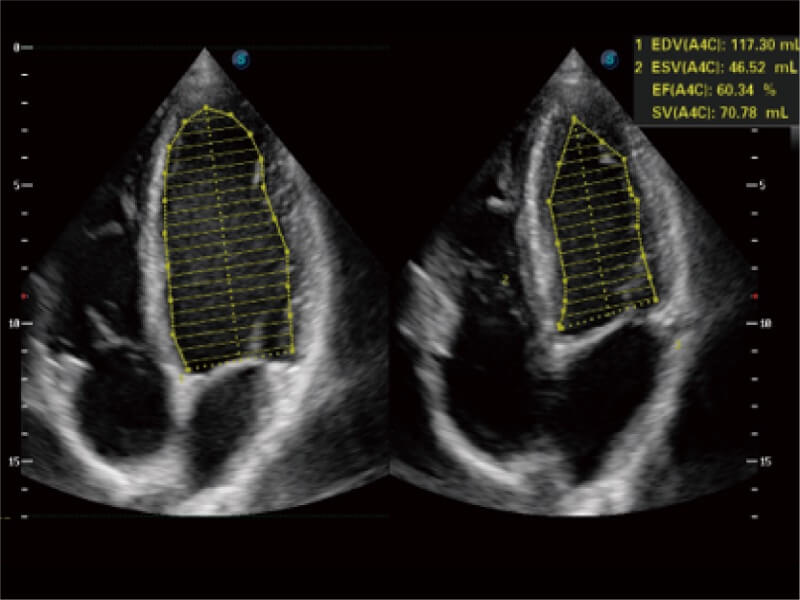

• Auto EF 心內(nèi)膜自動描跡

能夠基于左心室壁追蹤和辛普森法,自動計算射血分?jǐn)?shù),支持多個可移動點描跡,與手動測量相比,極大節(jié)省了動物醫(yī)生的時間和精力。